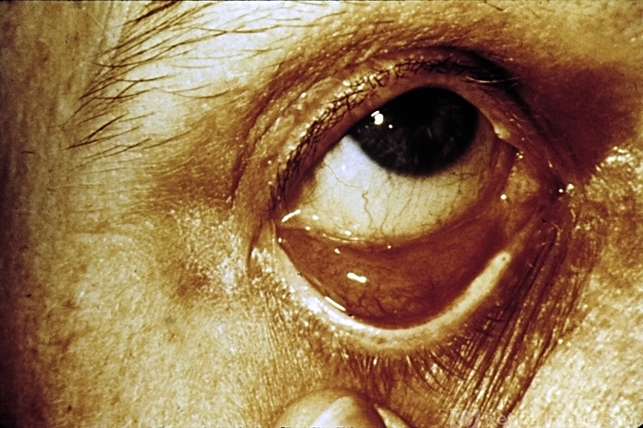

- tumor, conjunctiva

- Lymphoid tumor of the conjunctiva.